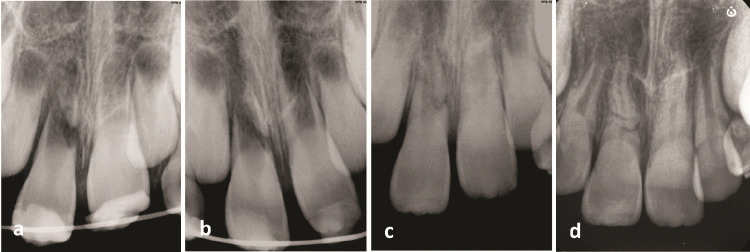

While traumatic injuries in the young permanent dentition are frequent, root fractures are relatively rare, particularly in immature teeth. This study reports the case of a 7-year-old boy who fell off a bicycle. Radiographic examination showed an immature right upper central incisor with fractures in the middle and along the root in an oblique and horizontal direction. Furthermore, there was an extrusion of the coronal segment from its original position. At the first appointment, the right central incisor was repositioned, and a semi-rigid splint was applied for four weeks. The patient was examined periodically for the following two years. After two months, the injured tooth was asymptomatic, with a reduction in probing depth from 8 mm to 2 mm along the tooth surface and a physiologic mobility. Although the injured tooth responded to the electric pulp test after nine months, it had no response to the cold test even after two years. The injured tooth showed continued root maturation of both coronal and apical fragments, although metamorphosis calcification and root canal narrowing were observed in conjunction with mild yellow crown discoloration. This report highlights the ability of Hertwig's epithelial root sheath and immature pulp to continue root development in fractured immature teeth.